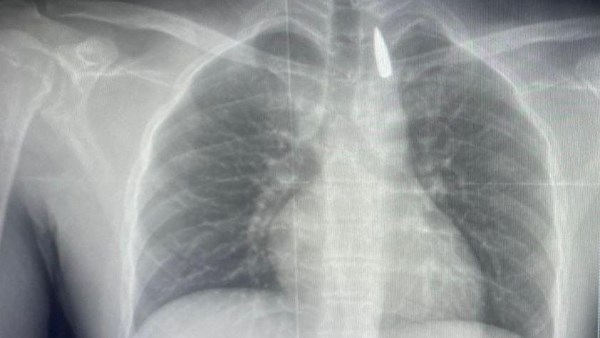

صورة من الاشعة

وأوضح الدكتور تامر عبد الله، عميد كلية الطب ورئيس مجلس إدارة المستشفيات الجامعية، أنه في يوم 21 أكتوبر 2025 تمكن فريق من أطباء قسم جراحة القلب والصدر والتخدير والمعاونين من إجراء جراحة دقيقة بالغة الخطورة لأحد المرضى المحجوزين من قطاع غزة، والذي كان قد تعرض لإصابة بطلق ناري في الرأس منذ فترة، استقر المقذوف على إثرها داخل تجويف القفص الصدري قرب الشريان الأورطي، وهو أكبر وأهم شرايين الجسم والمسؤول عن تغذية جميع الأعضاء الحيوية، وأضاف أن الفريق الطبي، رغم دقة الحالة وتعقيدها، نجح في استخراج المقذوف بأمان بعد عملية جراحية نادرة استمرت عدة ساعات داخل المستشفى الجامعي الجديد، حيث خضع المريض بعدها للرعاية الطبية اللازمة، وحالته حاليًا مستقرة وتحت المتابعة الدقيقة من الفريق المختص.